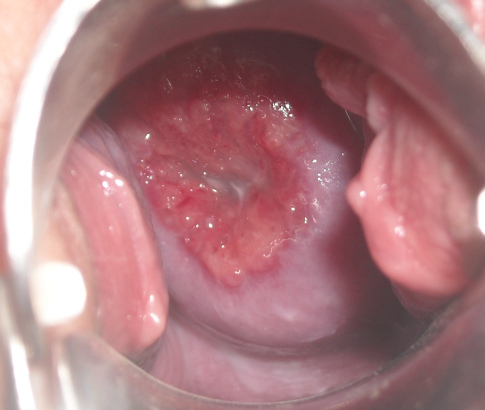

On pelvic exam, you see the following:

What conditions are in your differential diagnosis? (Chose any)

• Ectropion

• Cervical dysplasia (LSIL/HSIL)

• Cervical Cancer

• Cervical polyp

• Cervicisitis/STI